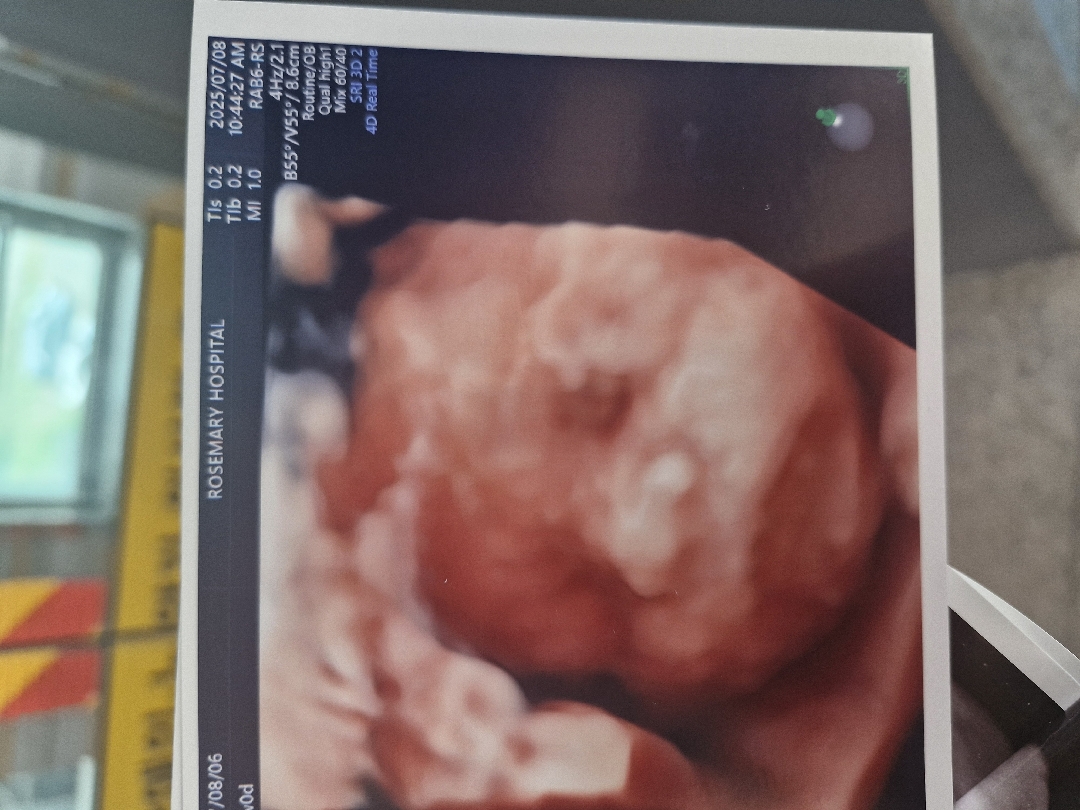

입체초음파 코봉이

27주입체초음파 봤는데 코가 원래이런건가요 걱정되네요 그치만귀여워요ㅠ

양수에 뿔어서 통통해보이는데 더 날렵해져요